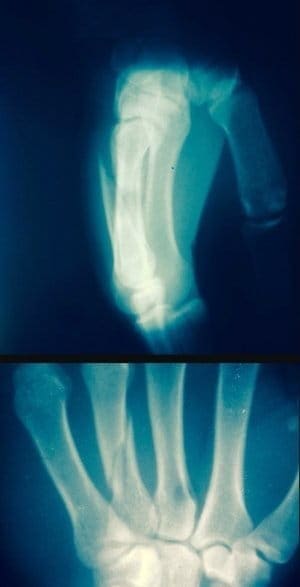

Турал Рагимов травмировал обе руки в поединке с Иваном Бучингером

Перелом пальцев со смещением на левой руке и разрыв связок на правой помешали россиянину Туралу Рагимову продолжить бескомпромиссную битву за пояс чемпиона M-1 Challenge...